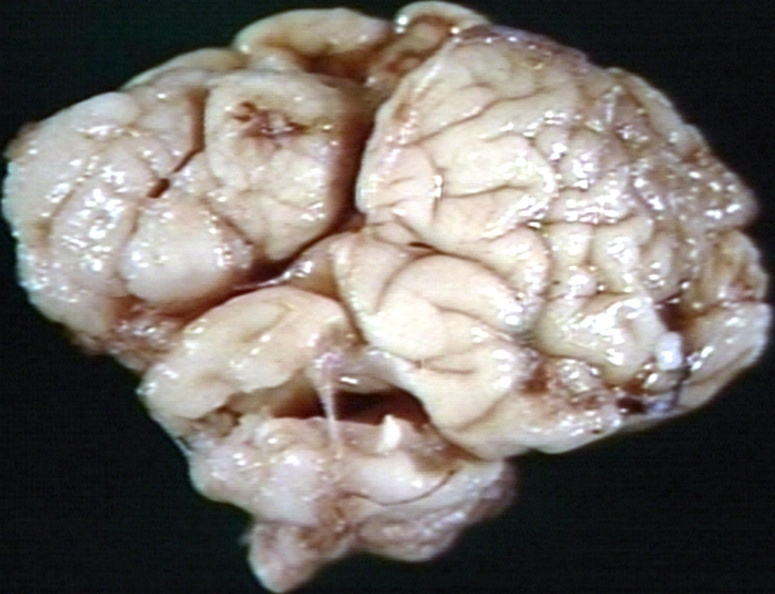

HISTOLOGY: CERVIX: DYSPLASIA, SEVERE, CERVIX

cervix, histology